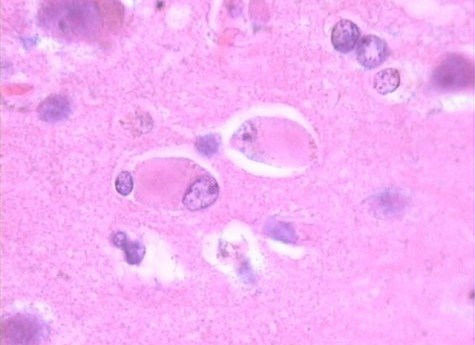

Es esencial comprender de manera amplia el proceso de la enfermedad, para que los médicos y los cirujanos reconozcan, diagnostiquen, y traten todas las enfermedades con precisión y competencia. Con…